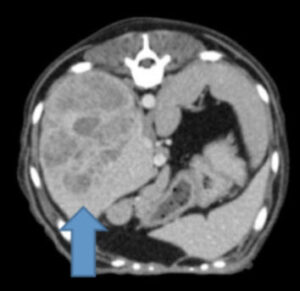

症例紹介 肝臓腫瘍の犬の1例 他院で肝臓に腫瘍があり、手術困難と言われ、セカンドオピニオンで来院された患者さんです。 レントゲン検査、超音波検査を行うと肝臓に大きな腫瘍犬の肝臓癌・肝臓腫瘍 ― 原因や症状、手術、治療法、改善・完治のヒント 犬が肝臓癌と診断されても悲観なさらないでください。 免疫の取り組みを行う事で体調が改善したりQOL(生活の質)を

犬 肝臓 腫瘍 エコー-犬の肝臓腫瘍~末期の症状と余命~ 内臓 (肝/脾/腎/他)の腫瘍, 肝細胞癌 肝細胞癌, 肝臓腫瘍 Tweet お腹のなかで最も大きい臓器は肝臓です。 そして最も多くの仕事をしているのも肝臓です。 そ肝細胞癌は犬の原発性肝臓腫瘍の中でもっと も多く見られる腫瘍で,肝臓腫瘍の50%にもな る肝細胞癌の53~%はマス状型で16~25% は結節状型,最大19%がび漫性型である2 マス状型肝細胞

動物がん診療サポート 池田雄太 はじめに 犬の肝臓腫瘍には様々なタイプが発生するが、その多くは肝細胞癌であり約70%を占める。 肝細胞癌は進行が比較的緩やかであり、無症状のことも多いた原因や症状、予防法などについて解説|いぬのきもちWEB MAGAZINE 獣医師監修|犬の肝臓病とは? 原因や症状、予防法などについて解説 肝臓は「沈黙の臓器」ともいわれ、病状があらわれにく犬の肝臓腫瘍の手術例 肝臓にできた肝細胞癌の手術例をご紹介します。 肝臓は胆のうを境に左区域と右区域に分けられます。 一般的に右区域にある腫瘍を摘出する手術の方が左区域のものより難